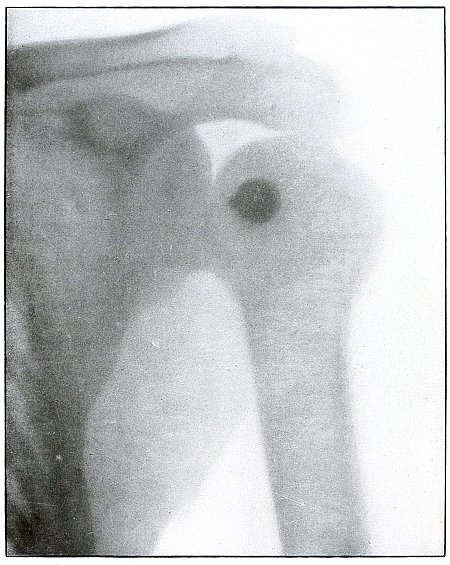

Gunshot wound, shoulder |

174 |

| 83. |

Gunshot wound, shoulder |

176 |

| 84. |

Gunshot wound, shoulder |

178 |

| 85. |

Gunshot wound, shoulder |